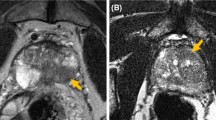

The early methods of estimating tumour volume were based on unenhanced T2W imaging alone. The addition of functional MRI sequences, such as diffusion-weighted imaging (DWI) and dynamic contrast-enhanced (DCE), improved the sensitivity and specificity for detection of clinically significant disease [48]. The effect on tumour volume assessment has been investigated in a limited number of studies [29, 32, 35] which find that T2W alone has a poor correlation with pathological volume (r = 0.21) [35]. DWI and ADC maps are consistently reported as the most accurate sequences with a high correlation coefficient (r = 0.75) [32]. Figure 1 shows an mp-MRI with an accurate tumour volume estimated on ADC map. DCE was the lowest performing sequence which is likely secondary to the lower spatial resolution of this sequence [29, 35].